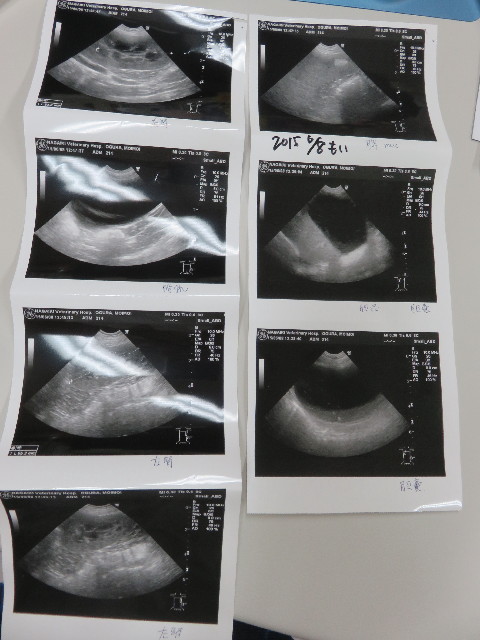

●エコー。

○胆のうに(前から)胆泥はあるが大丈夫。

○脾臓の前からある腫瘍のようなものは悪いものではないので大丈夫

○膀胱は右腎、左腎共にきれい

○膀胱もきれい

もいちゃんはなぜか?じっとしているだけで良い「エコー診断」が大嫌いですΣ(=゚ω゚=;)

お腹を出した体勢はとても緊張するようで...動かないように押さえているのにけっこう力がいります。